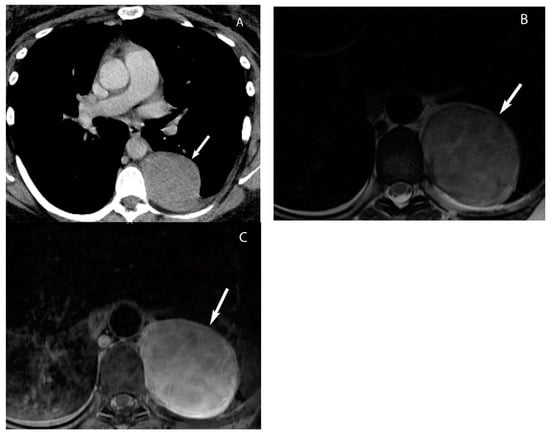

Visceral (Middle) Compartment

8. Cystic Lesions

9. Hypervascular Lesions

10. Esophageal Lesions